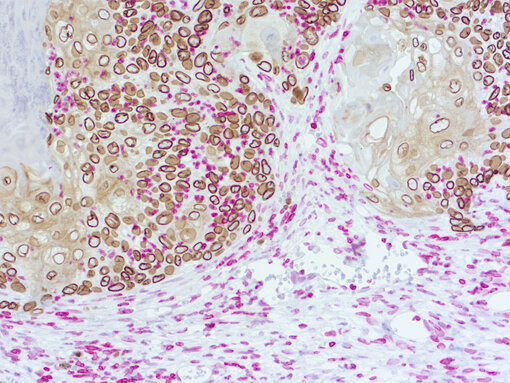

Immunohistochemical doublestaining of patient-derived lung cancer model

Figure 3a: Immunohistochemical doublestaining of patient-derived lung cancer model using rat anti-human Lamin B1 (cat.no. HS-404 017; DAB, brown color) and rabbit anti-mouse Lamin B1 (cat.no. HS-404 003; AP-RED, red color). Nuclei were counterstained with haematoxylin.